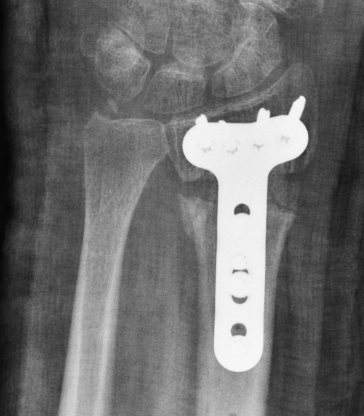

Volar opening wedge

Advantage

Volar approach and plate

Disadvantage

May require dorsal approach to bone graft

Technique

Vumedi volar osteotomy for distal radius fracture

Bed of FCR approach

- release brachioradialis

- protect structures with retractors

- perform osteotomy parallel to articular surface

- sufficient distal bone for screw fixation

- correct distal radius in two planes

- apply volar plate

- bone graft defect through radial aspect of wound

+/- dorsal approach to insert bone graft